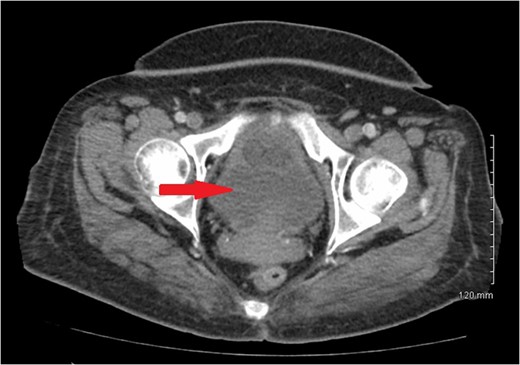

Computerized axial tomography scan of the abdomen revealed wall thickening or mass involving the proximal ascending colon with multiple subcentimeter lymph nodes within mesentery adjacent to this portion (Fig.

1). There was no evidence of metastatic disease. A 3.8 × 3.3 cm hypodense mass located in the central portion of the uterus was also noted (Fig.

Figure 1:

CT scan of abdomen showing ascending colon mass.